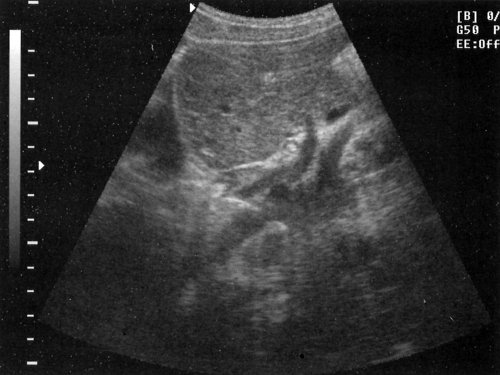

Сегментарное строение печени

Сегментарное строение печени — важная часть ультразвукового исследования, поскольку информация о том, в каком сегменте органа располагается поражение имеет большое значение. Печень может быть разделена печеночными венами следующим образом: правая вена делит правую долю на два сегмента — задний и передний (рис. 10) и левая вена разделяет левую долю на латеральный и медиальный сегменты (рис. 11). Теперь, если мы проведем продольные плоскости через левую, среднюю и правую главные воротные вены (рис. 12), то печень будет разделена на восемь сегментов (рис. 13).

Рис. 10. Подреберный косой срез через правую долю печени позволяет увидеть передний и задний сегменты (эхограмма).

Рис. 11. Медиальный и латеральный сегменты левой доли печени (эхограмма).